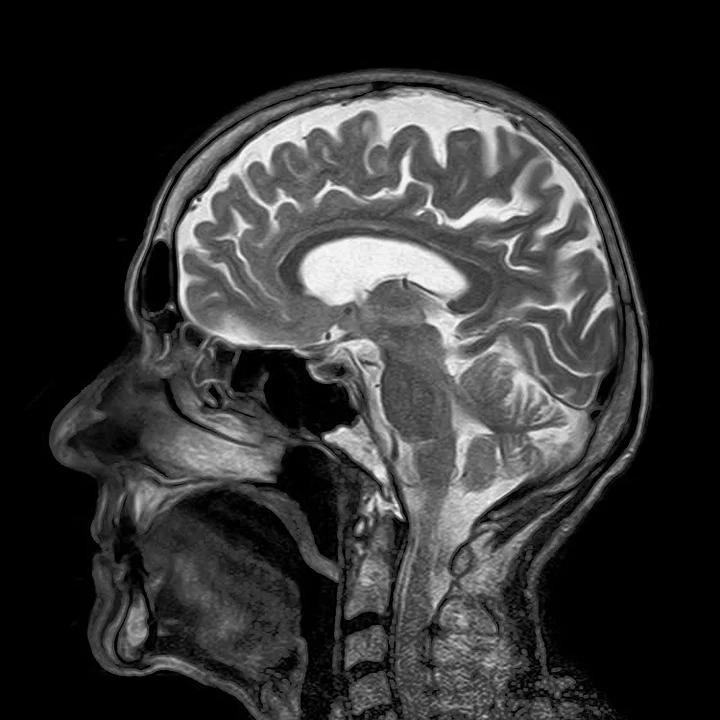

MRI(Magnetic Resonance Imaging) 라고 불리는 자기 공명 영상 촬영은 1980년대 중반부터 임상적으로 사용되었습니다. 자기 공명 영상이란 자석으로 구성된 장치 내에 사람을 눕히고, 자기장을 이용한 고주파를 쏘여 인체 내에 존재하는 수소 원자 핵에서 발생되는 신호를 분석하여 각 조직과 구조물들의 공명 현상의 차이를 계산하여 영상을 구성하는 것으로서 한마디로 자석을 이용한 촬영 방법인 것입니다. 기존의 진단 목적의 방사선 촬영은 대부분 방사선을 이용하였는데, 자기 공명 영상은 자석을 이용한 검사 방법이란 것이 기존의 방사선 촬영 방법과는 크게 다른 점입니다.

자기 공명 영상의 검사 대상은 매우 다양한데, 몇 가지 대표적인 예를 들면 다음과 같습니다. 뇌출혈, 뇌경색, 뇌종양 등의 뇌질환과 디스크 탈출이나 퇴행성 척추 질환의 진단에는 거의 필수적인 검사 방법이며, 무릎, 어깨, 손목, 발목, 팔꿈치 등등 관절의 이상, 스포츠 관련 외상, 골수염, 무혈성 괴사 등의 진단에도 필요한 검사입니다. 선천성 심장 질환, 심근경색증, 간의 종양, 사지의 종양, 종격동 질환, 두경부의 염증이나 종양의 진단에 있어서도 자기 공명 영상 촬영이 필요하며, 오래 전부터 자기 공명 영상을 이용한 혈관조영술이 가능하여 과거에 침습적인 방법으로 검사하던 혈관조영술 방식을 대체하기도 하였습니다.